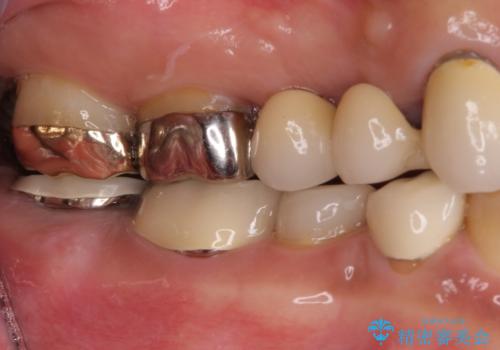

左上は当初治療予定ではありませんでしたが、クラウンの周りに汚れがたまっていることが気になってきたため、追加して治療を行うこととしました。

歯肉縁下にまで虫歯が及んでいたため、歯冠長延長術を行い、清掃性の改善を試みます。

仮歯がない状態を極力避けたいとのことで、外科処置を少しずつ進めていくことになり、治療期間は2年間を要しました。